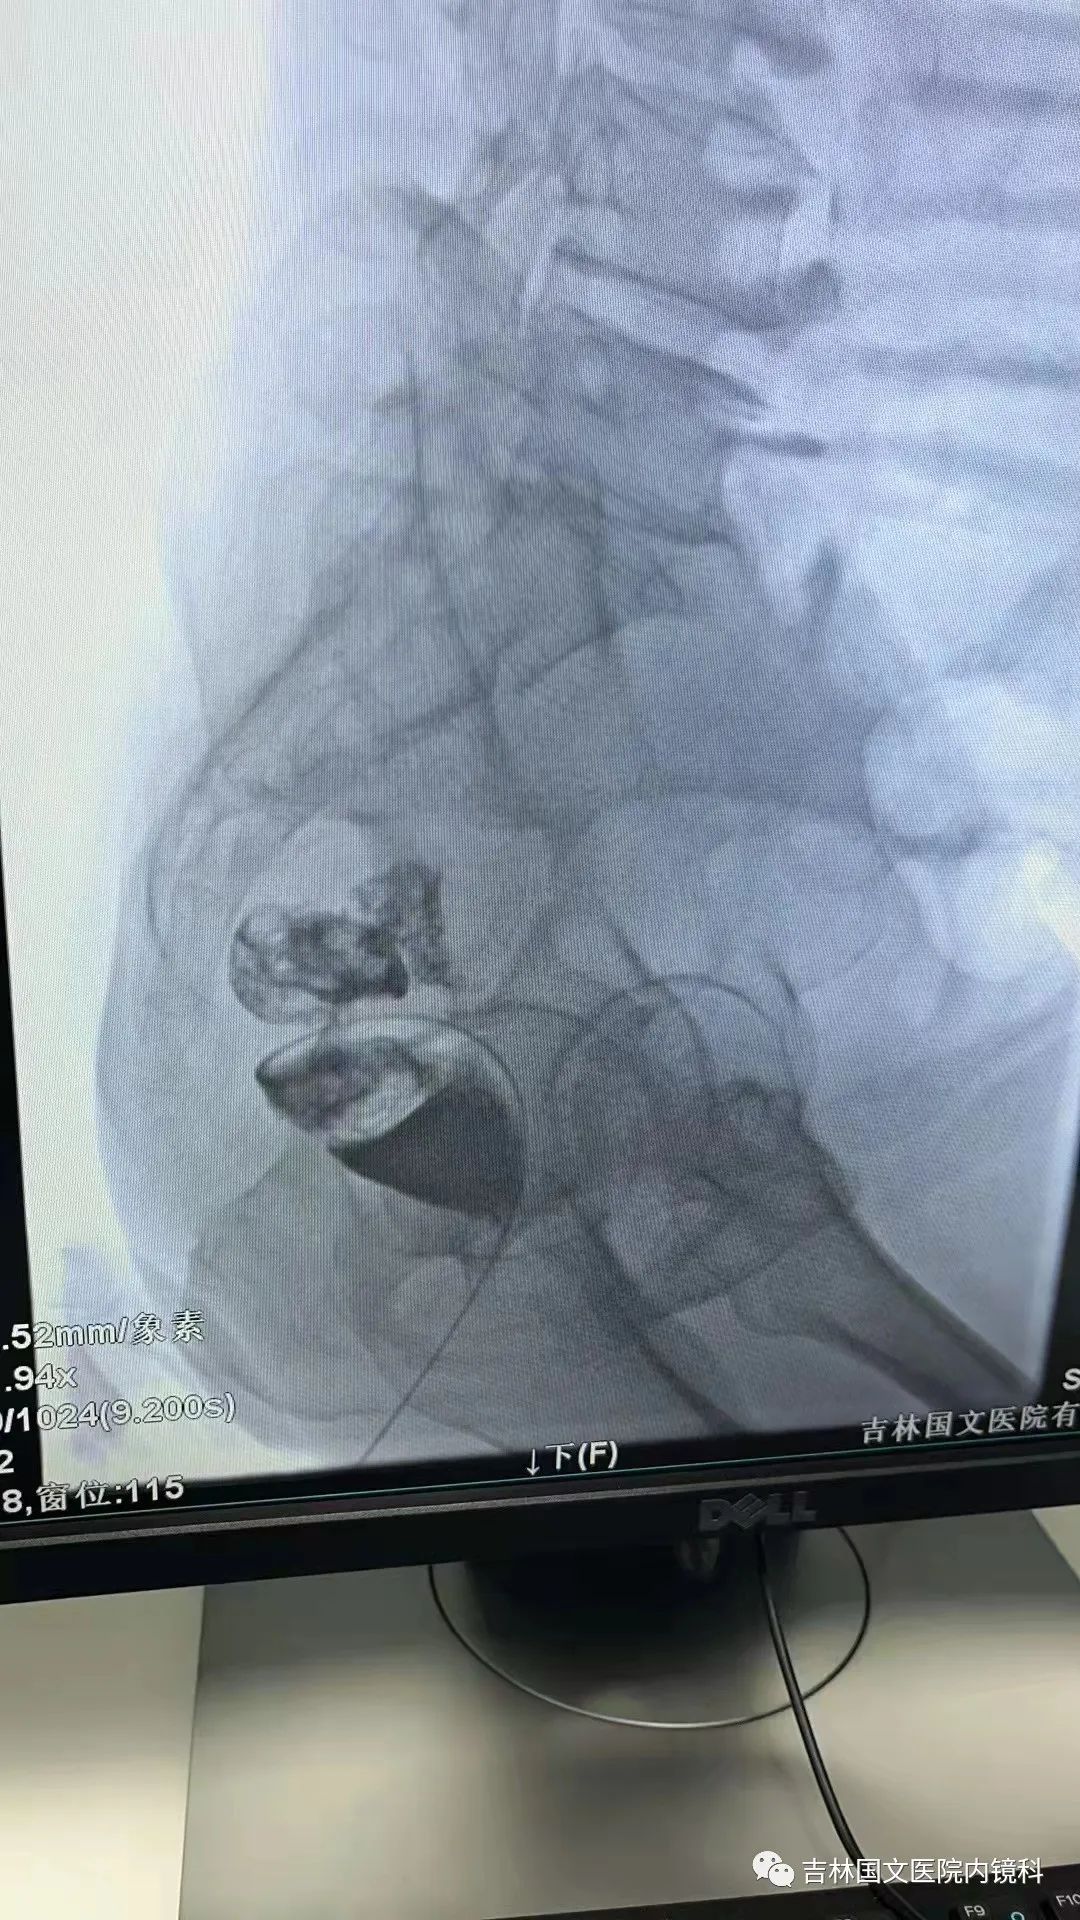

這是一位腸癌的患者,腫物生長在乙狀結(jié)腸,將腸腔堵得只剩一個小孔,糞便自然很難通過,腸梗阻的癥狀使患者十分難受,已多天未排氣排便,患者十分瘦削,開始侯主任未借助任何工具探查一番,結(jié)果就是腸道太迂曲了,實在無法順利將導(dǎo)絲置入,通過邢主任使用腸鏡在前面引路一直到達(dá)病變部位,這時候侯主任將帶有外套管的導(dǎo)絲從活檢口插入,外套管抵在小孔處,導(dǎo)絲順利進(jìn)入,第一步成功。第二步就是將支架順著導(dǎo)絲送入指定位置,又是一大難關(guān),導(dǎo)絲十分軟,缺乏支撐力,腸道的彎曲十分陡峭,一用力支架抵在腸道低處,患者痛感極強(qiáng),只能另想辦法,嘗試多次后,在兩位主任的豐富經(jīng)驗和堅持不懈的努力下,支架順利置入,為患者解除了痛苦。